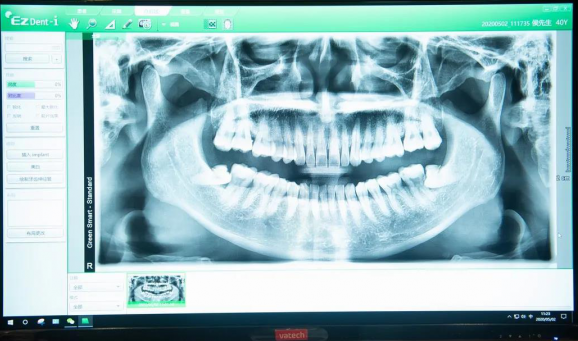

康达口腔专业CT全景口腔检查

拍摄3D CT全景照,帮助医生全面、清晰的了解口腔内部情况,可满足口腔项目的诊断需要,为后续治疗和矫正提供依据!